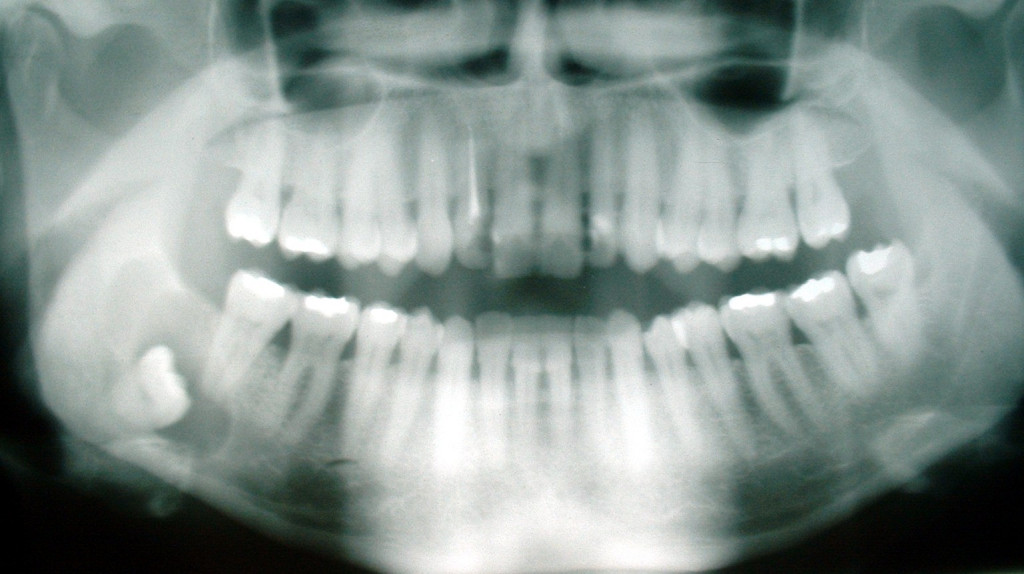

Related Images with How To Cure Wisdom Tooth Pain